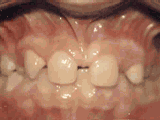

爱美之心,人皆有之~~5月份世界正畸日即将来临,暑假还远吗?分院提前给爱美的你准备好一份大大的福利,还等什么呢?抓紧约起来吧! 发现自己牙齿不整齐影响交际, 怎么还能与小伙伴愉快地玩耍? 无论是即将迈入新的年级还是即将面临找工作, 发现自己是“地包天”“龅牙妹”, 分分钟拉远自己和同龄人的距离! 这些难以启齿的牙齿问题, 想想就让人心碎,怎么办呢? 不要着急,不要慌乱! 这个时候, 你可能需要的就是牙齿矫正了~! 以下图片告诉你, 这些情况都适合去做牙齿矫正哦~! 前牙移位 症状表现:牙齿缺失、牙周疾病等导致相邻牙齿无秩序前突 牙列拥挤 症状表现:牙齿过多,牙槽骨过窄,使牙齿没有足够空间生长造成牙齿排列不齐 开颌 症状表现:通俗来讲就是咬牙时无法紧闭,上下牙齿中间有缝 上牙深覆合 症状表现:上牙边沿覆盖下牙超过1/3,俗话说的天包地 后天牙列稀疏 症状表现:疾病外因等造成的牙列稀疏,牙槽骨过长或牙齿缺失,导致排列太宽松,零零散散 前牙反合 症状表现:下牙边沿覆盖上牙超过1/3,俗话说的地包天 天生牙列稀疏 症状表现:天生的牙列稀疏,牙槽骨过长,牙缝过宽、牙齿较少(一般不缺牙),导致排列宽松,零零散散 以上几种情况有你么? 要知道一口整齐的牙齿 绝对能够把整体的颜值提升N个档次! 如果你不幸中招, 就好好利用这个正畸月, 来分院加入到正畸大军里吧! 牙齿正畸也叫做牙齿矫正,原理简单来讲呢,就是对牙齿施加一个合适的外力(一般通过矫正器来施加),这个力会通过牙齿传递到牙齿周围的牙槽骨上,使得代谢很活跃的牙槽骨发生改建,从而带动牙齿一起缓慢移动。其治疗效果有着肉眼可见的强大变化! 借此正畸月,分院为大家准备了正畸月大放价,暑假提前约的活动!!!如果还想了解更多关于牙齿矫正的信息,欢迎大家来到分院进行咨询哦~我们的专业团队会帮您定制最适合自己的矫正方案,活动月矫正方案免费送哦!定能助您改“斜”归“正”!露出灿烂自信的笑容!